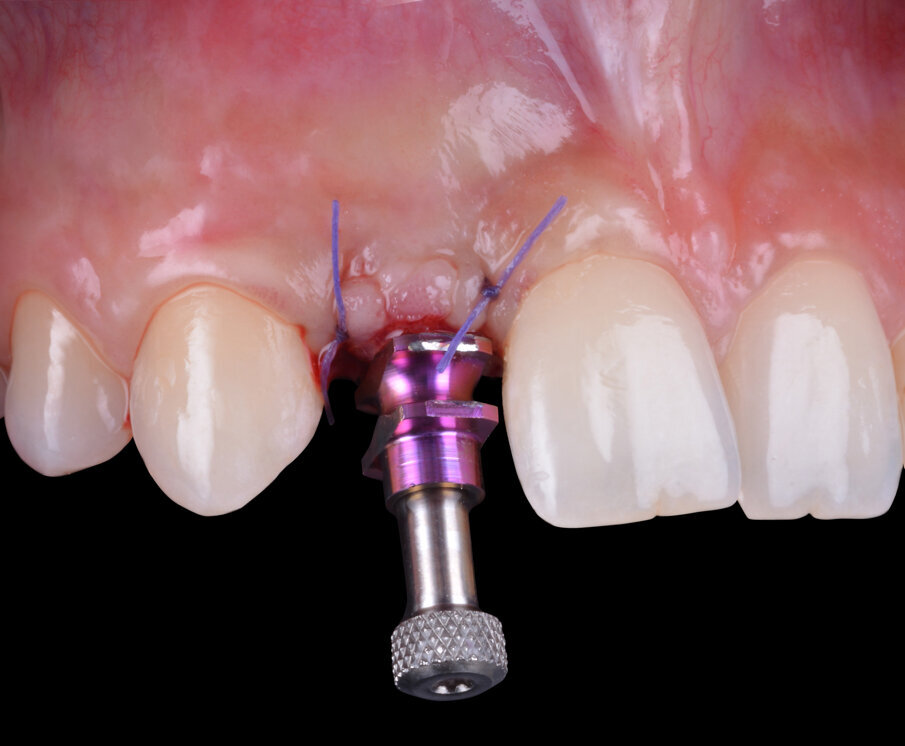

Le valutazioni preliminari evidenziano che in visione occlusale si è ottenuta una restitutio del profilo vestibolare dei tessuti molli e l’architettura della linea muco-gengivale è stata mantenuta tanto da rilevare un’elevata quota di banda cheratinizzata nella regione crestale del processo alveolare (Fig. 10); se non avessimo trovato una situazione clinica come quella descritta, si sarebbe configurata l’indicazione per l’esecuzione di un incremento a fini cosmetici della convessità buccale solitamente gestita con innesti gengivali autologhi o eterologhi. Si procede dunque con la riapertura disegnando un lembo mininvasivo crestale a spessore totale che, in prossimità della vite di copertura, consenta l’accesso per il recupero della stessa e la sua sostituzione con un healing abutment (avvitato a un torque di circa 15 N/cm). I tessuti cheratinizzati (ben rappresentati nell’aerea cervicale perimplantare) vengono stabilizzati grazie a due punti di sutura singoli staccati nella regione mesiale e distale all’impianto stesso. La necessità della paziente di risolvere precocemente i problemi causati da un Maryland bridge poco stabile ed esteticamente non soddisfacente a causa delle modifiche eseguite per salvaguardare le mucose in via di guarigione, rivestono un’indicazione per confezionare una corona in resina acrilica avvitata che viene posizionata il giorno stesso sull’impianto osteointegrato di 12 (Figg. 11, 12).

Fig. 10 - Situazione clinica a 6 mesi dell’inserimento dell’impianto.

Fig. 11 - Transfert da impronta in posizione.

Fig. 12 - Corona provvisoria avvitata in situ.